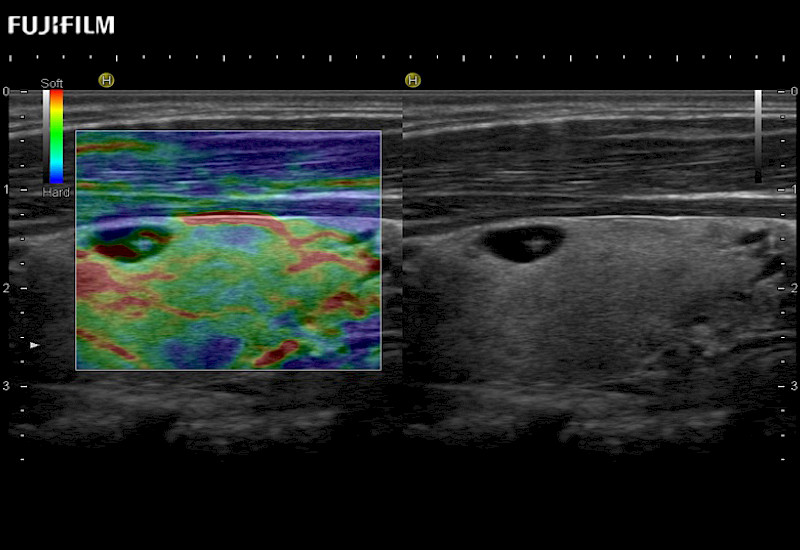

The ARIETTA 750 incorporates all of the proven technologies and functions that medical professionals have come to expect from Fujifilm Healthcare.

ARIETTA 750 is the definitive diagnostic ultrasound solution for any clinical setting - Private Office, Imaging Center, or Hospital. The ARIETTA platform provides the ultimate in clinical performance with its state-of-the-art features and large user-friendly display.

The ARIETTA 650 DI combines trusted Fujifilm Healthcare technologies and features tailored for surgical oncology.

Designed to meet the demands of surgeons, the ARIETTA 650 DI offers precise guidance. Its advanced capabilities and large, intuitive display offer accurate and efficient care in operating rooms and specialized surgical settings.

Guidance is the fundamental purpose for all of our surgical ultrasound technology. Fujifilm Healthcare is committed to designing tools that help neurosurgeons navigate inside the human body and provide the necessary information to immediately make critical surgical decisions.

With the ARIETTA Precision the next level of surgical ultrasound is here.